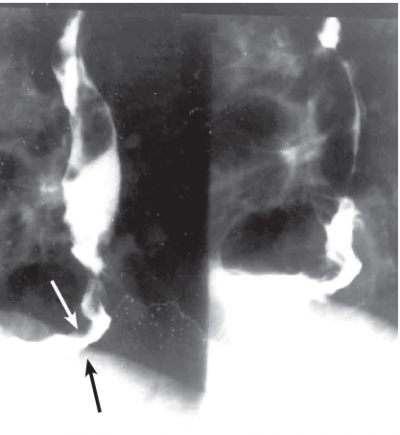

אדנוקרצינומה מופיעה בוושט הרחיקני. מוצאה מהאפיתל העמודי או מאיי האפיתל של Baret. לפי Neae, 10% מהחולים עם הוושט על שם ברט יפתחו אדנוקרצינומה. תיקון הרפלוקס במקרים אלה אינו משנה את המהלך. תצלום 16.1 מדגים את ביטויה בבליעת בריום.